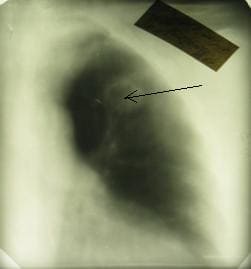

Центральная опухоль правого легкого больших размеров